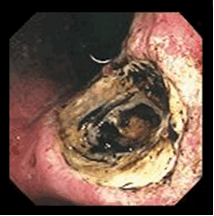

Рис.2. Пенетрация язвы желудка

Пенетрация язвы

Это тоже образование отверстия в стенке желудка или 12-перстной кишки. Однако оно открывается не в брюшную полость, а в расположенные рядом органы: поджелудочную железу, толстый кишечник, печень, малый сальник

Проявления зависят от того, в какой орган произошло прободение.

Общие симптомы: боли усиливаются и становятся постоянными. Они не проходят после приема пищи и употребления антацидов (альмагель, маалокс). Повышается температура тела.

Лечение неотложное, хирургическое.